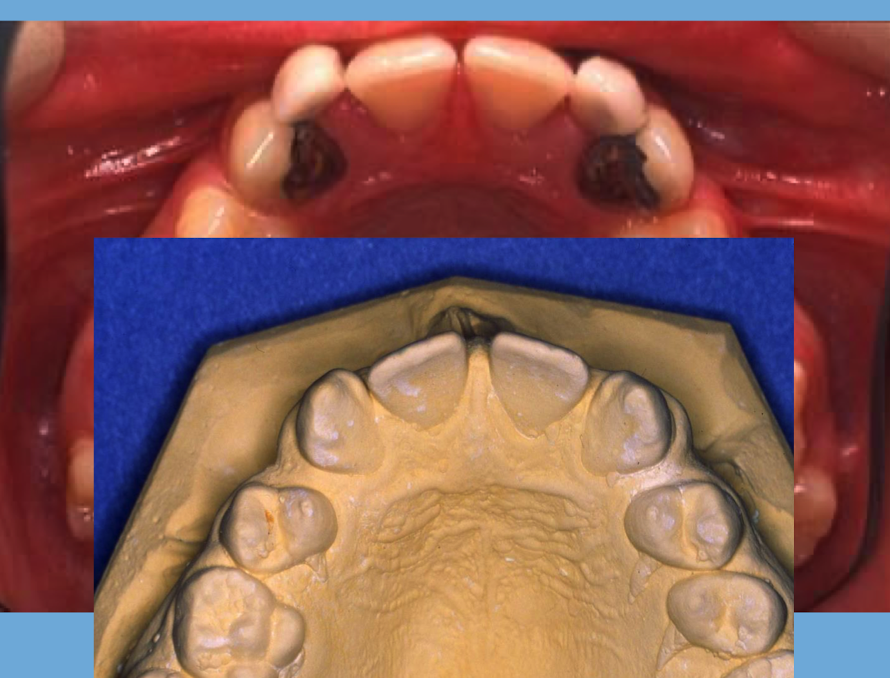

Tx option for this case:

- absent U2s

- ectopic canines

- midline diastema

A

1. extraction URb, ULb

2. sectional fixed appliance to close space between UR1 and UL1

3. allows eruption UR3 and UL3